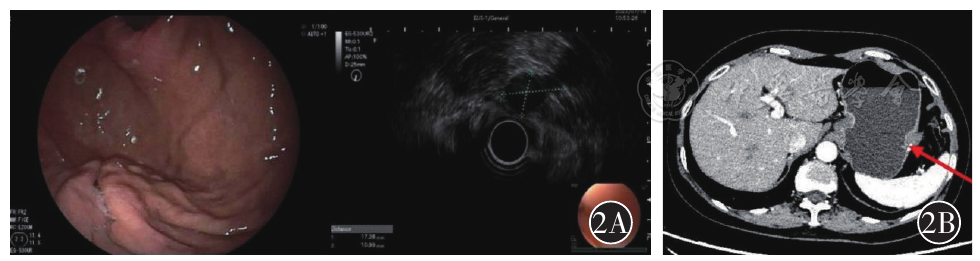

图2 A为超声内镜提示胃底体交界大弯侧术后瘢痕样改变;B为CT提示胃大弯侧软组织结节影